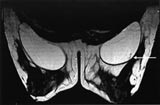

Det pågår en utstrakt forskningsaktivitet for å forbedre det diagnostiske potensialet til MR-undersøkelse av bryst. Ved MR-senteret i Trondheim har vi de siste årene særlig interessert oss for MR-teknikker som avspeiler kapillærgjennomblødningen i tumor, såkalt T2*-vektet førstepassasjebildedanning (fig 2). Bakgrunnen for å anvende denne teknikken er at kreftsvulster har flere og større kapillærer og dermed høyere kapillærperfusjon enn godartede svulster. Foreløpig synes det som om man ved denne teknikken kan påvise brystkreft med høy spesifisitet, men med en noe lavere sensitivitet enn den dynamiske T1-vektede teknikken (20). Siden T2*-vektet perfusjonsbildedanning avhenger av kapillærperfusjonen, kan metoden kanskje gi informasjon om tumorangiogenese (21) og dermed bli et hjelpemiddel både i vurderingen av kreftsvulstens metastaseringspotensial og i evalueringen av behandlingseffekten ved nye former for antitumorterapi som primært retter seg mot svulstens blodforsyning (antiangiogeneseterapi). MR-spektroskopi (MRS), hvor man benytter MR-teknikken til å få metabolsk informasjon fra svulsten, er en annen teknikk som i forskningssammenheng er brukt på brystsvulster. Metabolitten kolin, som inngår i cellemembranenes fosfolipidsyntese, er funnet i betydelige høyere konsentrasjoner i maligne enn i benigne brystsvulster, men det biokjemiske grunnlag for dette og den diagnostiske nytte av MRS i denne sammenheng trenger fortsatt evaluering (22, 23).

Tumordiagnostikk hos pasienter som har silikonimplantater som ledd i en brystrekonstruksjon eller av kosmetiske grunner, er vanskelig med mammografi. Dersom heller ikke ultralydundersøkelse, eventuelt med ultralydveiledet aspirasjonscytologi, gir avklaring, kan det hos denne pasientgruppen være indikasjon for MR-undersøkelse ved tumormistanke. Ved vevsprøvetaking fra tumorsuspekte områder nær implantatet kan det være en risiko for å punktere silikonprotesen. Våre egne erfaringer viser at MR-veiledet biopsi eller finnålsaspirasjon av tumorsuspekte områder er et alternativ i slike tilfeller (fig 3).